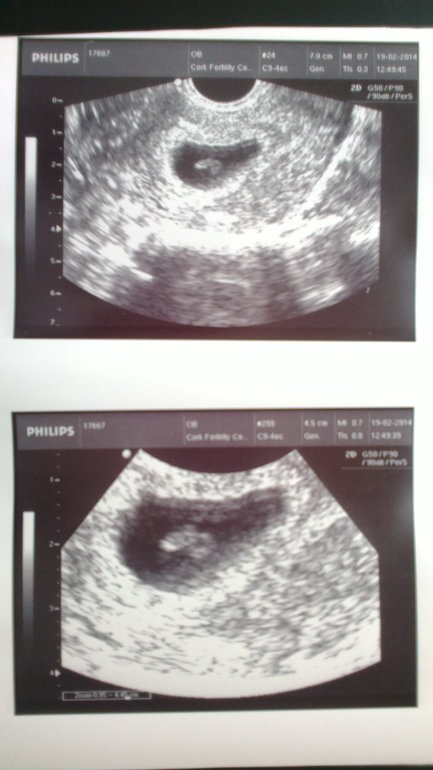

Уколы стимуляции делал муж. Верили, что от его рук зависит 80 % успеха. На все сканы ходила сама и носила его баночку с шустриками тоже сама в день пункции. Хоть в этой стране всегда муж должен сопровождать жену и принимать решение должны вместе. Перенесли мне двоих малышиков и началось затяжное ожидание. Тесты полосатились, но я постоянно переживала, а вдруг что-то сорвется. На подтверждающем УЗИ увидели одну крошку и сердечко. Муж дрожал от волнения. Но опять-таки, по инструкции о наступлении Б могут выдать заключение только после второго УЗИ на 8 нед. Вот завтра настанет тот день. Верю, моей крошке там понравилось и она никуда не делась за две недельки.

Надеюсь крошка моя завтра мне улыбнется и мы увидемся с ней уже через 7 месяцев.